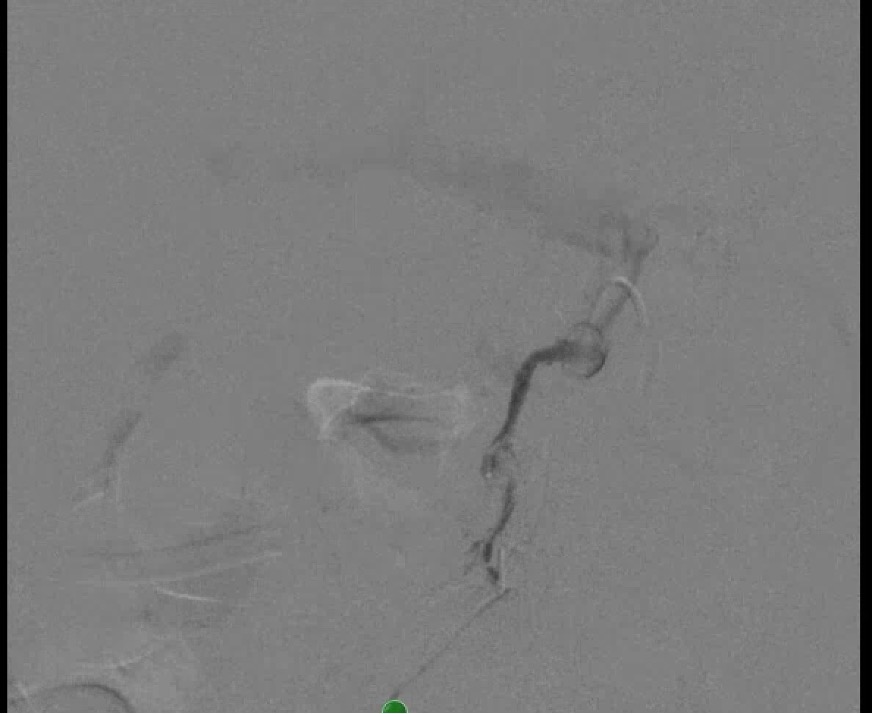

Angiogram showing contrast pick up in the portal vein after injecting contrast in the pancreaticoduodeal artery confirming a fistulous connection